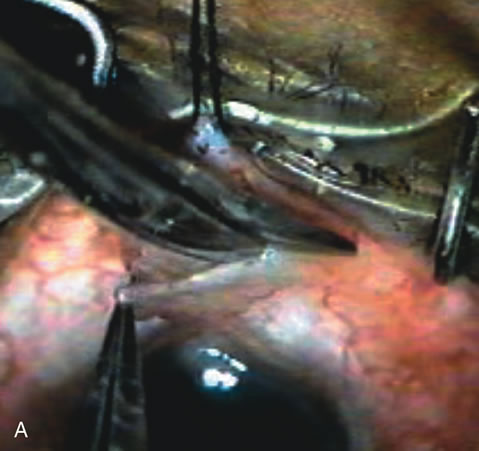

Fig. 7. Phacotrabeculectomy adjacent to a failed filter in cataractous eye. The ability to combine small-incision cataract extraction with trabeculectomy all through the same incision adjacent to the failed filter allows the surgeon to work in a familiar superior area. Avoiding incisions into the existing bleb decreases conjunctival buttonholes, hypotony, operating room time, and subconjunctival bleeding. A. Appearance of failed bleb with exposure of superior temporal quadrant gained with a corneal traction suture. B. Prepare a limbus-based conjunctival flap and a scleral flap. C. This bleb is at high risk to fail again justifying the need for MMC, 0.2 mg/cc applied on a pledget for 4 minutes. D. Insert the keratome and perform phacotrabeculectomy in the usual fashion.

The inflammation associated with lens extraction at any site usually causes complete failure of a marginal functioning bleb. In addition, pressure reduction by medical means is usually minimal in these recalcitrant cases, and combined surgery is indicated. In the past, these cases were approached with large-incision ECCE, clear corneal cataract incision, and bleb revision. Drawbacks included those mentioned earlier for large incision clear corneal cataract extraction, and bleb revision is often associated with conjunctival buttonholes, wound leaks, subconjunctival hematoma, destruction of friable sclera, and associated hypotony. With the advent of modern-day cataract surgery, a phacotrabeculectomy is often possible adjacent to the failed filter (Fig. 7). The ability to combine cataract extraction with implant and filtration surgery all through the same small incision has greatly improved outcomes for patients with marginal preoperative filters. There are several other viable options in this case. If the surgeon elects to remove the cataract through a temporal clear corneal incision, the bleb may be revised or a new adjacent filter fashioned. As mentioned earlier, revising a failed filter is technically challenging. If the surgeon believes it is not feasible to revise the filter or fashion a new one, a glaucoma drainage implant is a reasonable option combined with temporal lens extraction.172